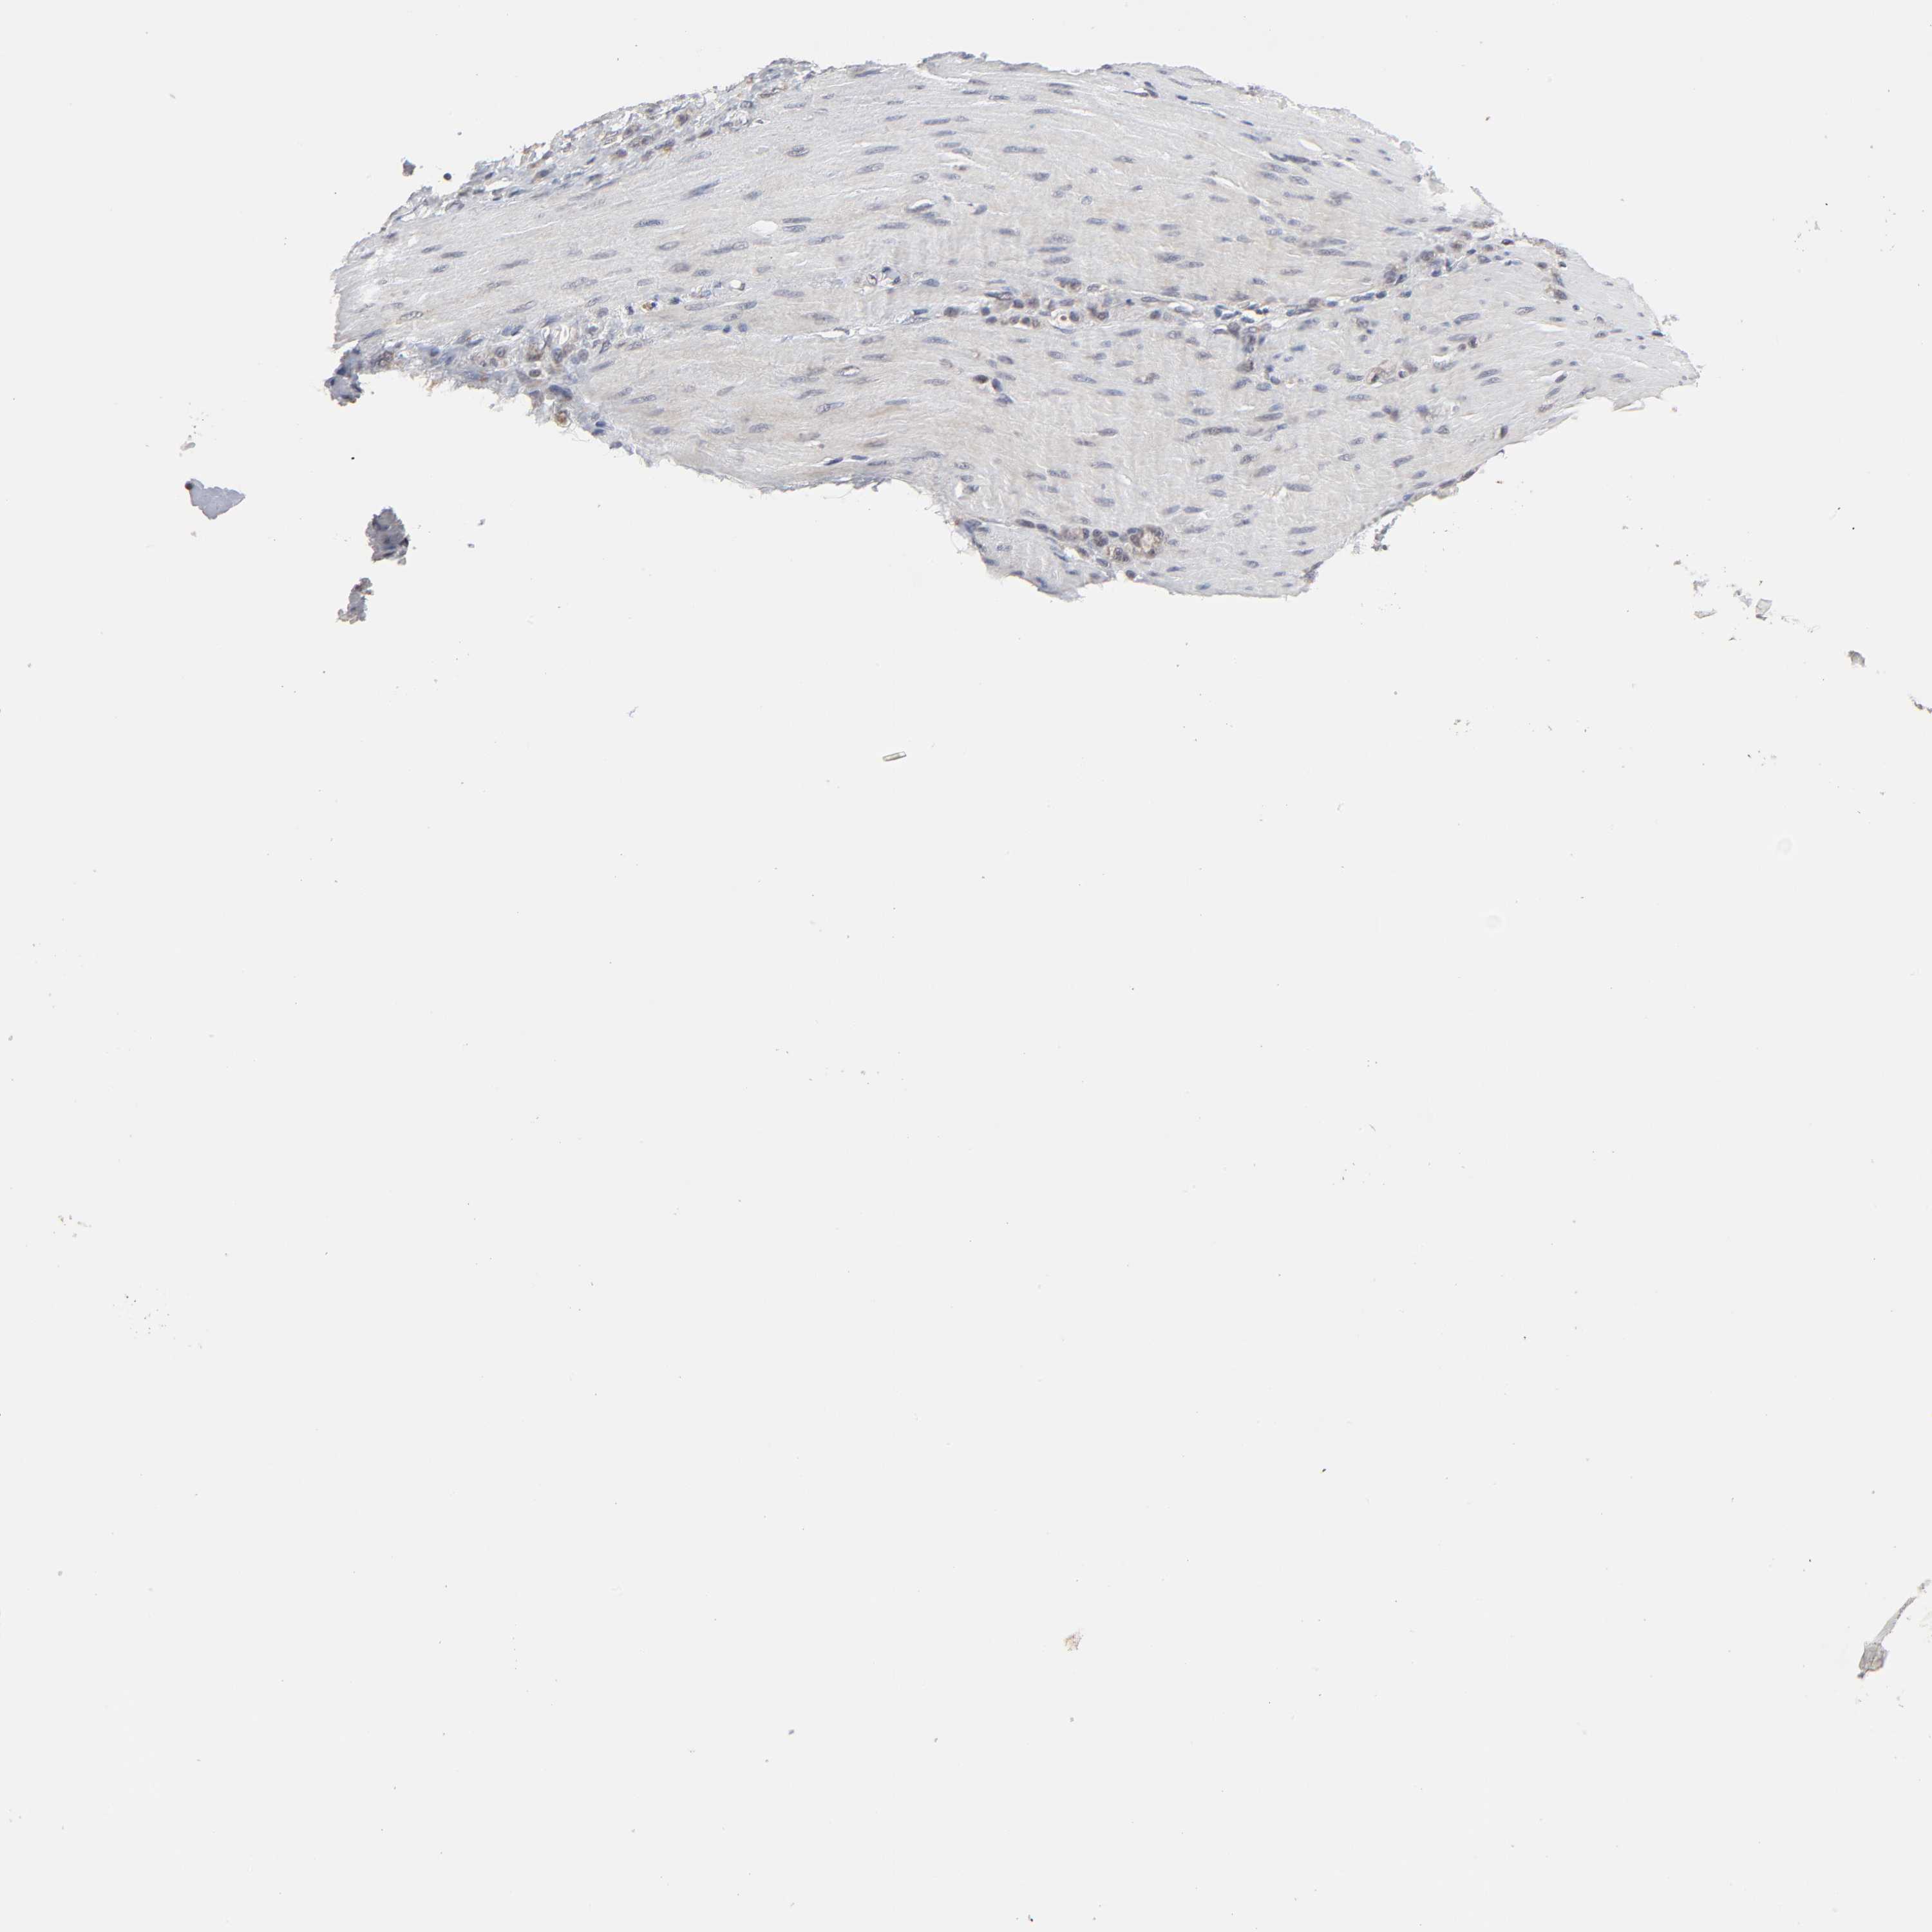

STOMACH CANCER - Protein expressioni

A mouse-over function shows sample information and annotation data. Click on an image to view it in a full screen mode. Samples can be filtered based on level of antibody staining by selecting one or several of the following categories: high, medium, low and not detected. The assay and annotation is described here.

Antibody stainingi

Antibody staining in the annotated cell types in the current human tissue is reported as not detected, low, medium, or high, based on conventional immunohistochemistry profiling in selected tissues. This score is based on the combination of the staining intensity and fraction of stained cells.

Each image is clickable and will lead to virtual microscopy that enables deeper exploration of all samples and also displays staining intensity scores, fraction scores and subcellular localization as well as patient and tissue information for each sample.

Antibody HPA004171

Staining

High

Medium

Low

Not detected

Intensity

Strong

Moderate

Weak

Negative

Quantity

>75%

75%-25%

<25%

None

Location

Nuclear

Cytoplasmic/membranous

Cytoplasmic/membranous,nuclear

Adenocarcinoma, NOS

Adenocarcinoma, High grade